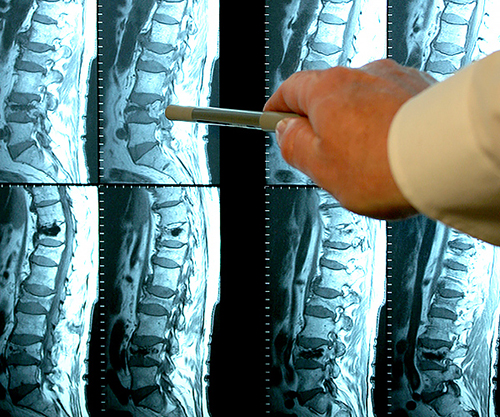

โรคข้อที่พยายามจะ "วินิจฉัย" แยกกันในประเทศไทยนั้น ในประเทศญี่ปุ่นได้รวมเข้าเป็นหนึ่งเดียวมานานแล้ว นั่นก็คือ "การสะสมเกลือในข้อ" ซึ่งอาการดังกล่าวได้แก่:

- เกาต์

- ข้ออักเสบ

- ข้อเสื่อม

- กระดูกสันหลังเสื่อม

- รูมาตอยด์

- กระดูกพรุน

- ถุงน้ำข้ออักเสบ

- เยื่อหุ้มข้ออักเสบ

- ถุงน้ำไขข้อ (ก้อนซีสต์)

นี่เป็นเพียงรายชื่อโรคอย่างย่อเท่านั้น โรคอื่น ๆ ล้วนเป็นเพียงกลุ่มย่อยของพยาธิสภาพหลักทั้ง 9 ประเภท เช่น โรคข้อสะโพกเสื่อม (Coxarthrosis) ก็เป็นชนิดหนึ่งของโรคข้อเสื่อม (Osteoarthritis) เป็นต้น